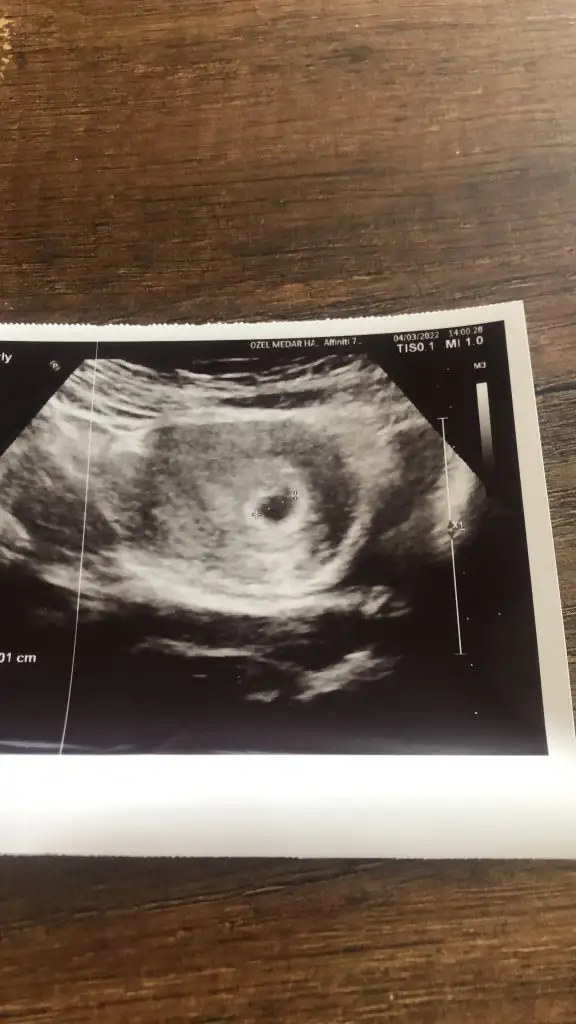

Merhabalar arkadaşlar biliyorum tahminler zor 10 haftada ama biraz eğlence olsun diye düşüncelerinizi merak ediyorum 5 haftalık kese iken ve 10+2 deki fotoğraflarımızı attık teyzelerim var mı tahminleriniz?

Tinkerbelso Popüler Üye Anneler Kulübü Kayıtlı Üye 26 Nisan 2017 868 1.599 113 41 5 Nisan 2022 Konu Sahibi Konu Sahibi S3lin8767 #2 Erkek sanırım, kızlar yuvarlak oluyormuş sağlıkla gelsin